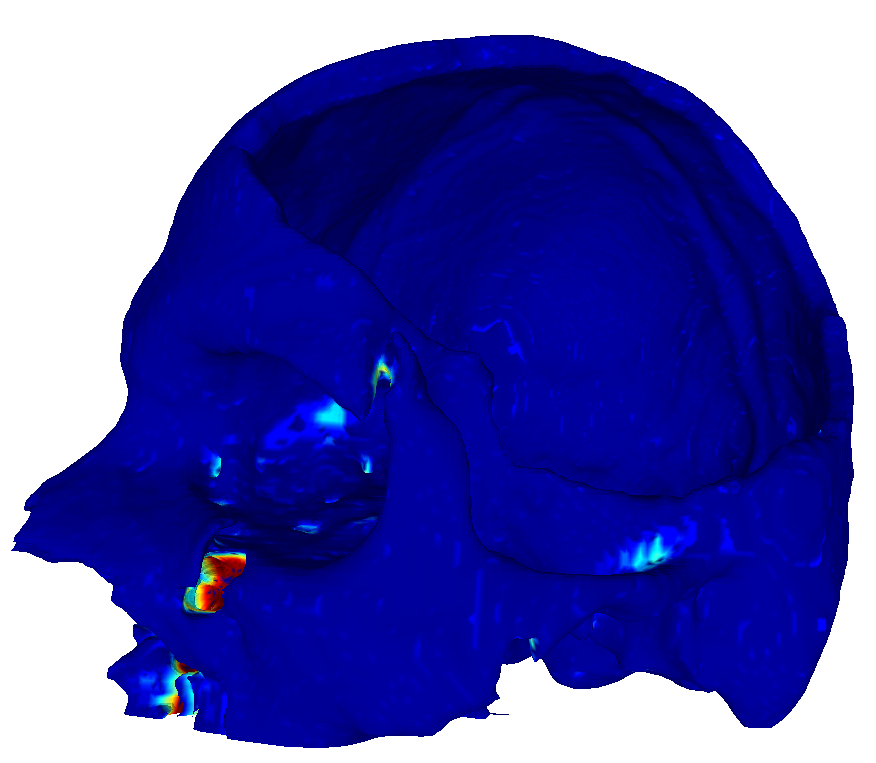

22 scans were randomly selected as test subjects for the experiment, leaving 177 skulls for model training. Using convolutional kernels of size 3 in all the CNN models results in the 3D model having the same number of trainable parameters as the sum of the three orthogonal 2D models. The comparison between the MV ensemble and the 3D approach can therefore be considered an ablation study to an extent. CutCNN models also have a similar number of parameters, the only difference being the final edge probability output layer. Quantitative comparison of results of each method are presented in Figure 4 and Table 1. Further qualitative results are shown in Figure 5 and 1.

CutCNN segmentation framework resulted in a performance gain in all cases in terms of every metric used in the experiment over standard CNN approaches. The output of CNN object probability map often contains errors near external objects or smaller tissue defects as these are scarce in the training data distribution. However, the graph-cut optimization guides the resulting binary segmentation towards a spatially consistent and compact shape, often eliminating these artifacts if a detected edge corresponds mostly to the correct object boundary. This effect is further illustrated in Fig. 1.

Our second observation is that using 3D convolutional kernels has a rather small effect on the final segmentation precision quantitatively compared to the MV approach. However, although the quantitative difference is small, for applications in medical additive manufacturing, it is important to avoid ragged segmentation output which may result from MV CNN in areas of lower model certainty. These include for example teeth, which are challenging to detect, especially when the lower and upper teeth are in contact (see Figure 5 a), or maxillary sinus, which is often enclosed in order to improve mechanical stability of the manufactured model (see Figure 5 b). Therefore, 3D U-nets are often considered necessary to avoid these discontinuities caused by slice-by-slice processing.